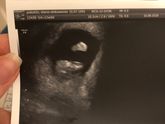

Прошли!!! Мы прошли 1 скрининг?? господи, девочки, я расплакалась? в том году у нас на скрининге все и закончилось(( пришла плохая кровь, мы сделали прокол, нам подтвердили СД((( потом сдали с мужем кариотипы, все в норме, оба здоровы..видимо случайность … Читать далее